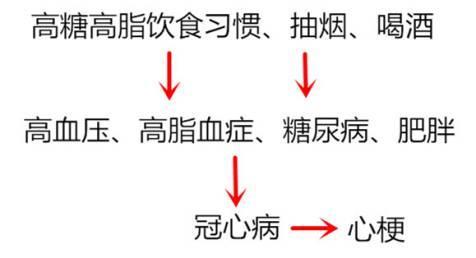

(1)“三高”人群

运动太少,暴饮暴食,吃得太油,是大城市年轻人的通病,于是高血脂、高血压、糖尿病、肥胖也容易盯上这些年轻人。而高血脂、高血压、糖尿病和肥胖等是心梗的加速器,这几项基本决定心梗出现早晚的问题。

戒烟戒酒,吸烟和大量饮酒可通过诱发冠状动脉痉挛及心肌耗氧量增加而诱发急性心肌梗死。

饮食上要清淡饮食,控制食盐量,食盐过多会导致血容量增加,直接增加心脏的负担;多吃新鲜果蔬,避免食用高脂肪的动物内脏;避免食用高甘油三酯,高胆固醇的食物。

积极治疗三高

控制血压、血糖、血脂以及体重,三高在一起,会加重加速动脉粥样硬化形成,加重加速斑块形成,为心肌梗死埋下祸根。定期监测血压、血糖、血脂,早预防、早发现、早控制,把三高导致的心肌梗死风险降到最低!